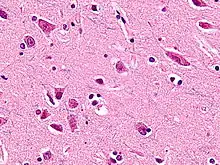

Von Economo neurons, also called spindle neurons, are a specific class of mammalian cortical neurons characterized by a large spindle-shaped soma (or body) gradually tapering into a single apical axon (the ramification that transmits signals) in one direction, with only a single dendrite (the ramification that receives signals) facing opposite. Other cortical neurons tend to have many dendrites, and the bipolar-shaped morphology of von Economo neurons is unique here.